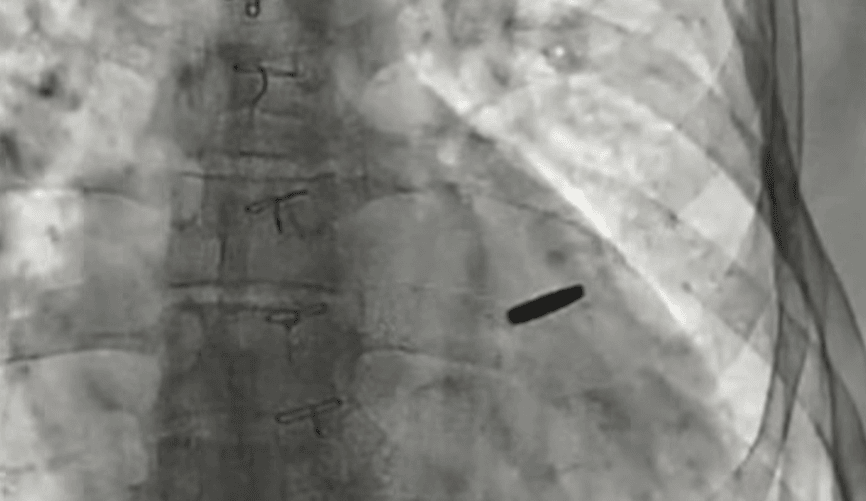

Куля нічого не пошкодила й увійшла неглибоко. Оперували чоловіка без зупинки серця менш ніж годину, а витягували уламок за допомогою спеціального магніту.